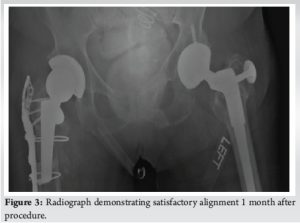

The surgical approach began with an incision on the lateral aspect of the right leg, with careful dissection through the iliotibial band, which was incised longitudinally. A soft vastus approach to the femoral shaft was utilized, reflecting the vastus lateralis in an L-shaped flap. During the procedure, a transverse fracture of the right proximal femur was discovered at the subtrochanteric region, which involved the cylindrical stem. Both the proximal and distal portions of the femoral stem were found to be well-fixed with excellent bone ingrowth. Due to the significant morbidity that would result from removing the proximal portion of the femoral stem, the decision was made to only remove the distal portion. A cylindrical trephine was used to core out the distal segment of the stem, with minimal bone loss. In addition, a 15 mm sliver of bone was removed from the distal portion of the proximal femoral stem, which was intussuscepted into the intramedullary canal of the distal femur. This achieved an excellent apposition of the bony surfaces while maintaining rotational alignment. A long periprosthetic proximal femoral plate with a trochanteric extension was placed along the lateral cortex of the femur to span the fracture site. Subsequently, a cortical strut allograft was applied along the posterior aspect of the femur. Proximal fixation was achieved using multiple circumferential cables, as well as both non-locking and locking screws with compression across the fracture site, provisionally maintained using a clamp. Distal fixation was reinforced with additional bicortical screws and cables. Intraoperative radiographs demonstrated optimal reduction of the fracture, with the femoral stem tip positioned below the fracture site (Fig. 2). The lateral proximal femoral plate spanned the fracture site at over 1.5 times the canal diameter, in accordance with conventional recommendations for bypassing the fracture, ensuring stability and proper alignment. Postoperatively, the patient was made toe-touch weight-bearing on the right leg for the first 6 weeks, with progressive weight bearing as tolerated during the following 6 weeks. Physical therapy continued throughout this period (Fig. 3).

Six-month post-operation, the patient reported no discomfort in the right hip and was able to return to her nursing facility. X-rays showed that all hardware was intact and demonstrated good bone healing.